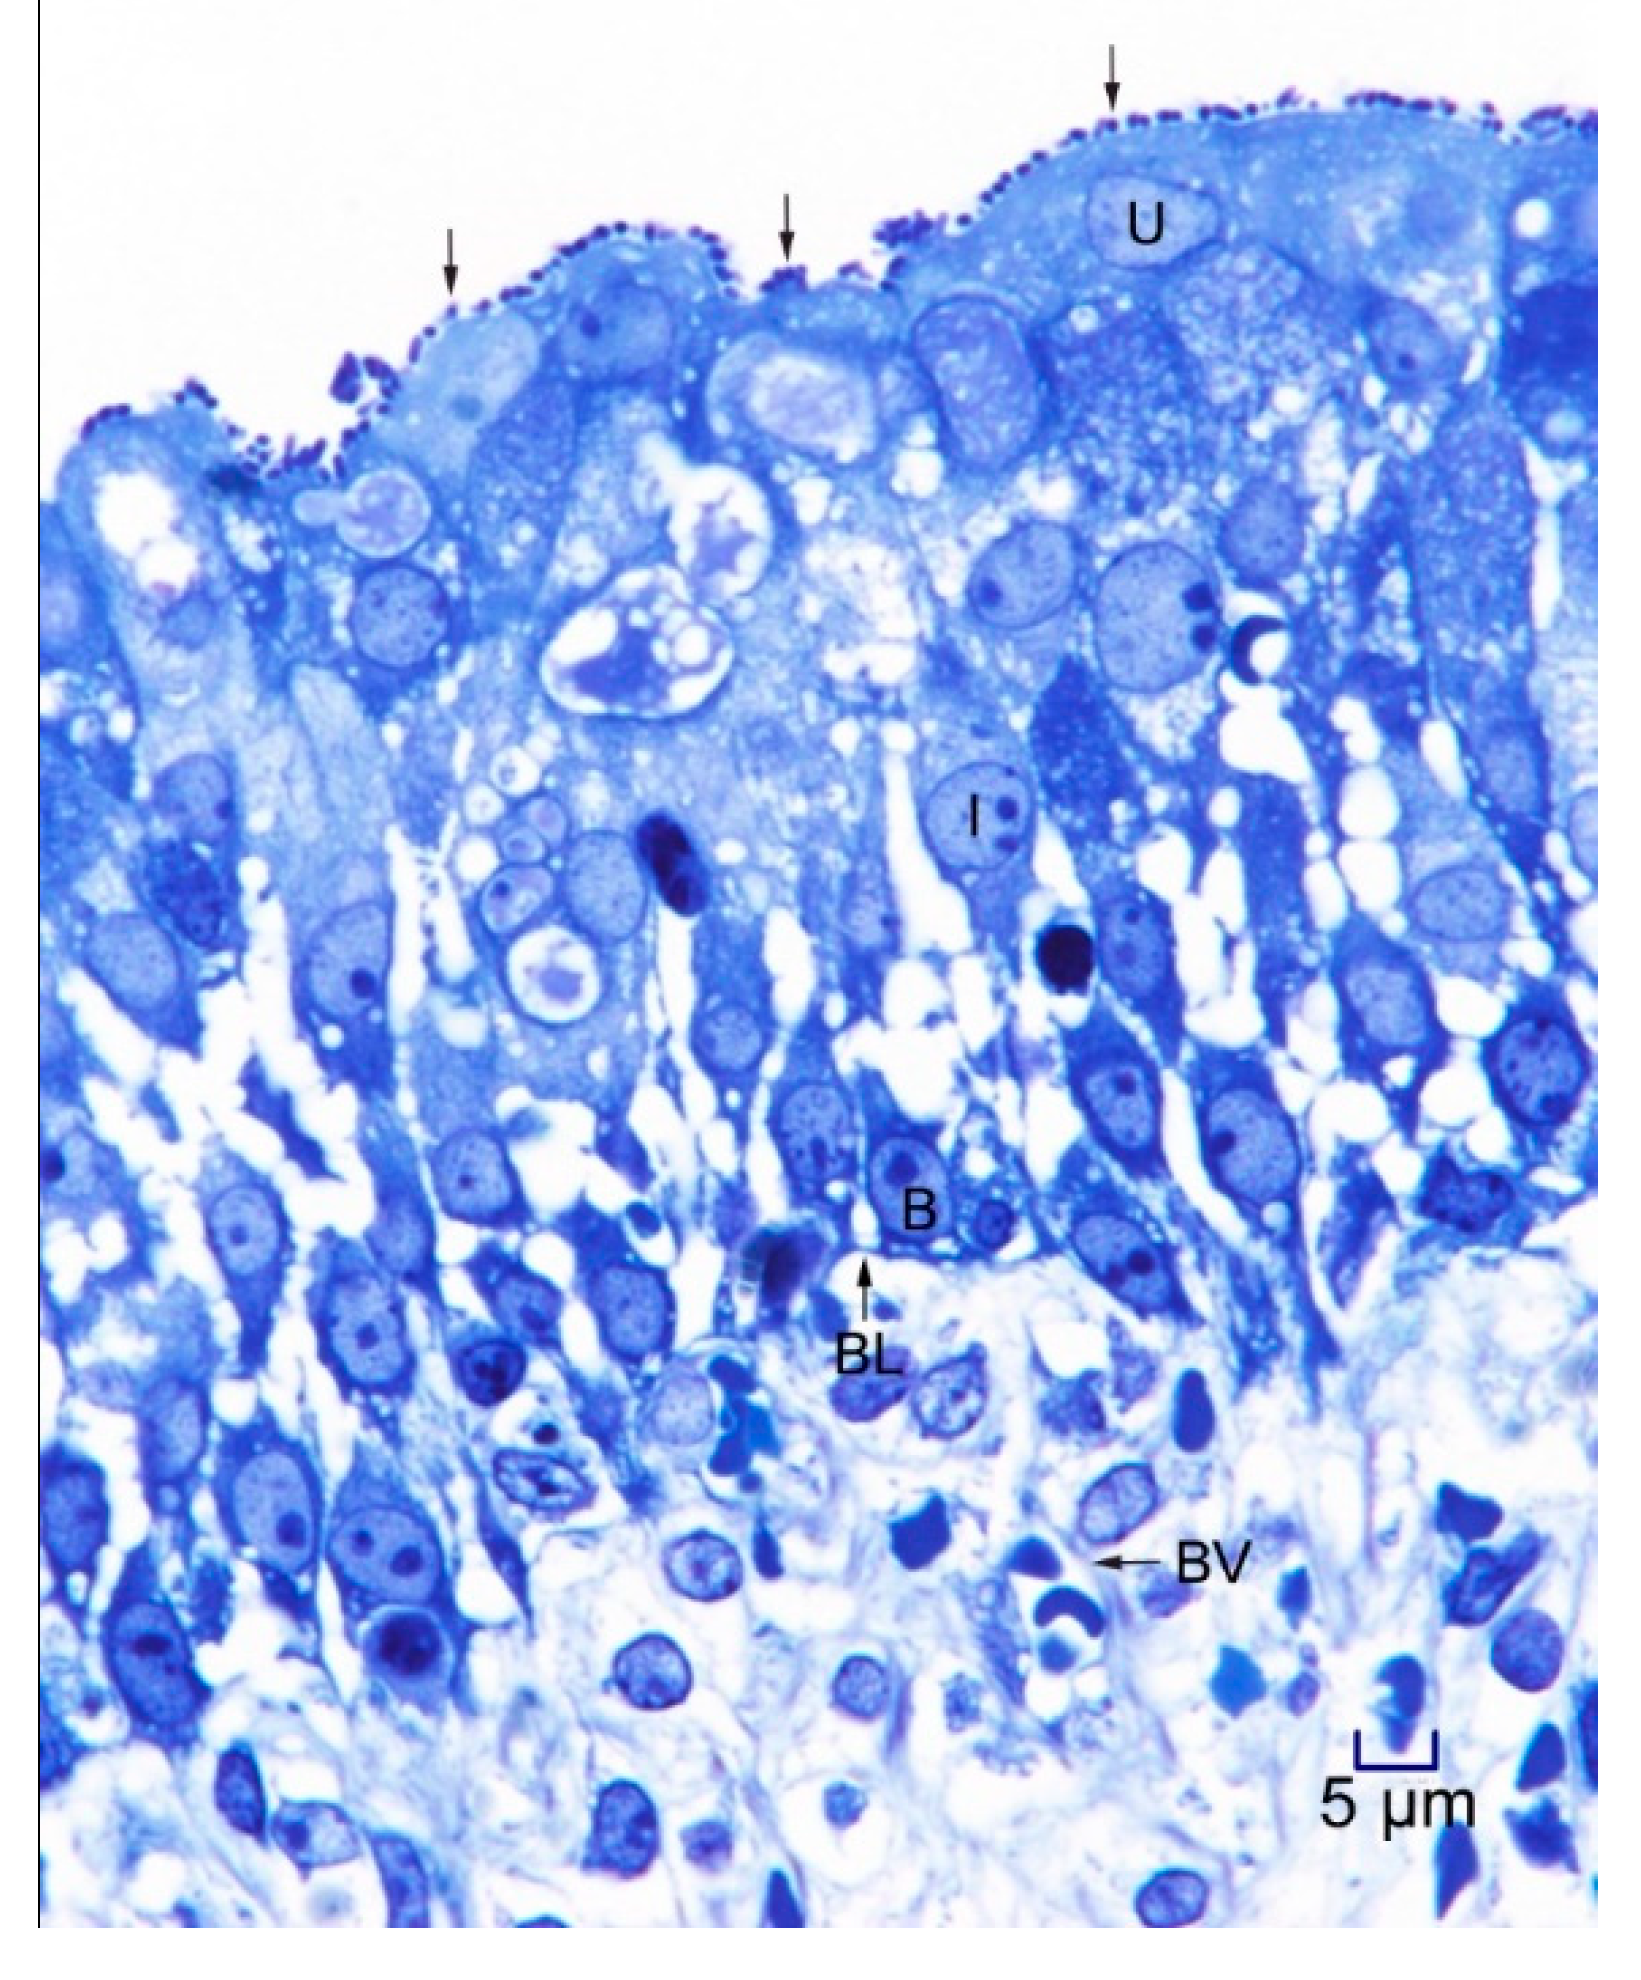

In 1-μm thick Araldite sections of urinary bladder prepared from tissues originally contained within the paraffin blocks [25], bacteria were detected only in piglet 15627 (Figure 1). In this piglet, in which bladder sections were oriented such that all three cell layers (basal, intermediate and superficial or umbrella) of the urothelium [26,27,28,29] were visible, bacteria, corresponding to bovine-origin strain 2891, were diffusely adherent to the apical surfaces of umbrella cells. By TEM, bacterial cells were found intimately attached to pedestals (Figure 2, Figure 3 and Figure 4). Some bacterial cells appeared to be attached to microplicae, preceding pedestal formation (Figure 4).

Figure 1.

Light photomicrograph of toluidine blue-stained, 1-μm thick, Araldite section of urinary bladder of piglet 15627, 8 days post-inoculation (PI) with bovine-origin strain 2891. EHEC O157:H7 bacterial cells (arrows) are diffusely attached to the apical surfaces of superficial uroepithelial (umbrella; U) cells. The section includes all layers of the mucosa, with U cells, intermediate cells (I) and basal cells (B) present, as has been described in pigs [26,27], humans [28], and other species [29]. Basal lamina (BL) and submucosa with structures such as blood vessels (BV) are also seen in the section. Photomicrographs stained with hematoxylin and eosin (H&E) showing purulent cystitis, and positive immunohistochemical staining for E. coli O157 antigen of a larger sample of the same piglet specimen were shown in the previous publication [25]. Bar = 5 μm.